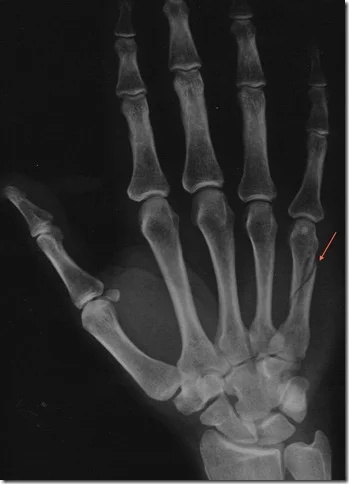

Metacarpal Fractures

- Careful about rotational malalignment

- Check rotation by flexing the fingers

Finger malrotation

- Undisplaced / or only one MC

- Treatment by cast / or splint

- Displaced / Rotated / Multiple

- Treated by internal fixation (screws / plates / wires)